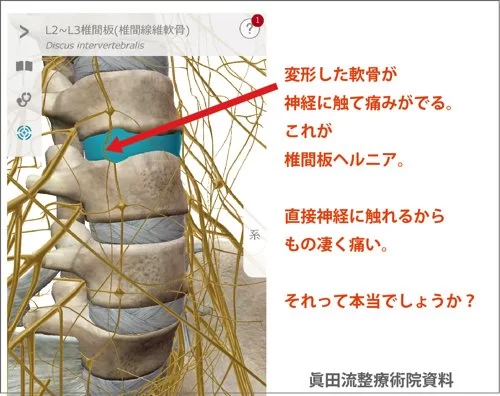

そもそもヘルニアとは?

椎間板ヘルニアに関して簡単に説明すると

こんな感じで骨と骨の間に軟骨があります。

そして腰骨の周りには神経がいっぱい走っているのです。

そんな場所でこんな感じで軟骨が飛び出して神経に触れると

痛みやシビレが出る。それが一般的なヘルニアだと思って下さい。

もし、本当に飛び出した軟骨が神経に触れて痛みが出ているのなら

その上を軽く叩いたら

激痛で気絶するレベルの痛みではないかと・・・

思ったりします。

ヘルニアは誤診?

MRIの検査ではヘルニアの状態が確認出来ているので

誤診ということは無いと思います。

ヘルニアは飛び出した軟骨が神経に触れているから

腰や足に痛みやシビレが出ると言われるのですが。。。

今回のお客様の例で考えると

飛び出した軟骨が施術で元に戻って痛みが消えたのか

そもそも飛び出した軟骨と腰や脚の痛みは関係ないのか

ご判断はお任せいたします。